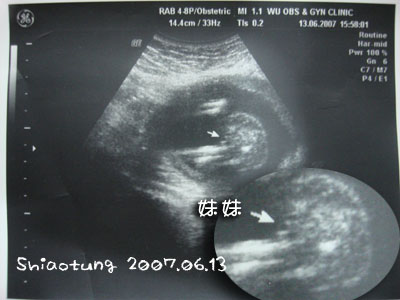

看不懂吼?

我也看不懂...

放大給你們看!

箭頭地方指的就是女生的生殖器。

醫生還是說:三條線就是妹妹。

我怎樣看都看沒有...

一直想像但是有點難理解,

不過我覺得三個黑點還比較像!!

反正...就是這樣啦!

看不懂的話就不用懂啦~